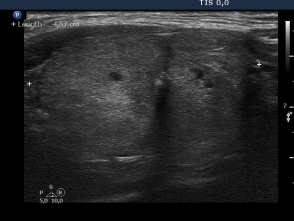

First session of sclerotherapy (1st row of images)

Clinical presentation: a 27-year-old woman was referred for evaluation of a multinodular goiter. The lesion in the left lobe has increased in the past two years and caused neck discomfort.

Palpation: a not firm nodule in the left lobe.

Functional state: euthyroidism with TSH 0.93 mIU/L, FT4 14,3 pM/L.

Ultrasonography: the thyroids were echonormal. There was a small lesion with a maximal diameter of 7 mm in the right lobe and a larger nodule in the left lobe. Both were echonormal.

Aspiration cytology resulted in benign colloid goiter.

We suggested surgery because of the compression signs. The patient told us that she is a cook in a seafarer and she has the opportunity to miss from the work only for a couple of weeks in the subsequent years. We advised ethanol sclerotherapy. Six sessions of ethanol was given. A total amount of 13.7 mL ethanol was administered in six session in 5 weeks.